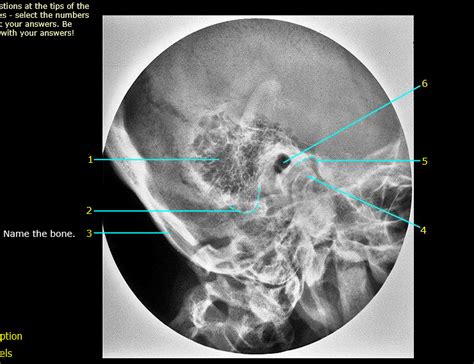

The Anatomy of Mastoid Air Cells

Let’s get down to the nitty-gritty, guys, and talk about the anatomy of mastoid air cells . These aren’t just single, big blobs of air; they’re actually a whole network of interconnected cavities. Think of it like a honeycomb inside the mastoid bone. This process, the mastoid process, is that pointy part of the temporal bone that sticks out just below your ear. Inside this process, you’ve got these spaces, called cells, that are lined with the same kind of mucous membrane that lines your middle ear. The size and number of these cells can vary a ton from person to person. Some people have really extensive, large air cells, while others have fewer, smaller ones. This variation is totally normal and is often determined by genetics. The pneumatization process, which is basically how these air cells develop and fill with air, is super important. It starts in infancy and continues for years. If this process is interrupted or doesn’t happen fully, it can affect how susceptible you are to ear infections. The mastoid air cells are also strategically located. They’re right next to the middle ear cavity, separated by a thin layer of bone. This close relationship is key to understanding why infections can spread so easily. The middle ear is where your eardrum and the tiny little bones that transmit sound are located. When an infection takes hold in the middle ear (think of a nasty bout of otitis media), the inflammation and fluid can easily make its way into the mastoid air cells. This can lead to a cascade of problems. The anatomy is also significant because of what’s nearby. The temporal bone is a real neighborhood of critical structures. You’ve got the auditory ossicles (malleus, incus, and stapes) in the middle ear, the cochlea and semicircular canals of the inner ear responsible for hearing and balance, the facial nerve (which controls muscles in your face), and major blood vessels like the sigmoid sinus. Any inflammation or infection spreading into the mastoid air cells can potentially impinge on or damage these vital components, leading to serious complications like hearing loss, dizziness, or even facial paralysis. Surgeons have to be incredibly careful when operating in this area because of this intricate anatomical arrangement. They need to navigate the air cells while preserving the integrity of the surrounding structures. Understanding this complex network of air cells, their variable nature, and their intimate connection to the middle ear and other critical cranial structures is fundamental to grasping the clinical significance of the mastoid air cells. It’s a testament to the intricate design of the human body, where seemingly simple air pockets play such a vital role in overall ear health and can become a focal point for pathology when things go wrong.